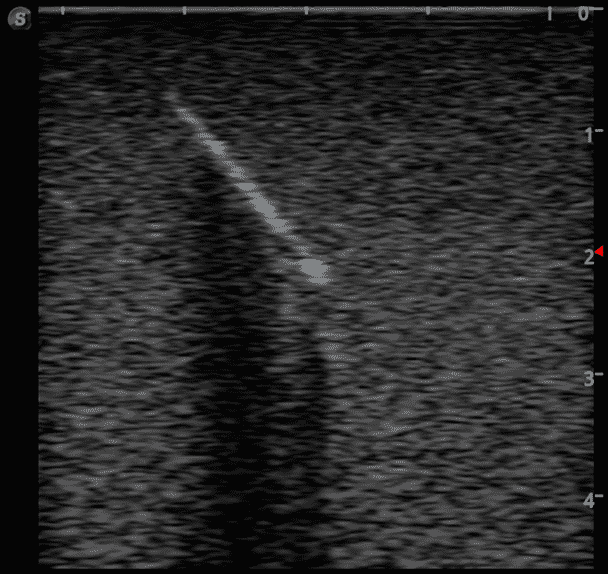

Foreign Body Ultrasound Training Model

Model TYE4033

This training block is designed for training users in the techniques associated with ultrasound guided foreign body identification, targeting, and retrieval.

· High-quality ultrasound images

· Objects found in the human body including:

Glass shards

Wood splinter

Bullet

Plastic fragments

Metal fragments